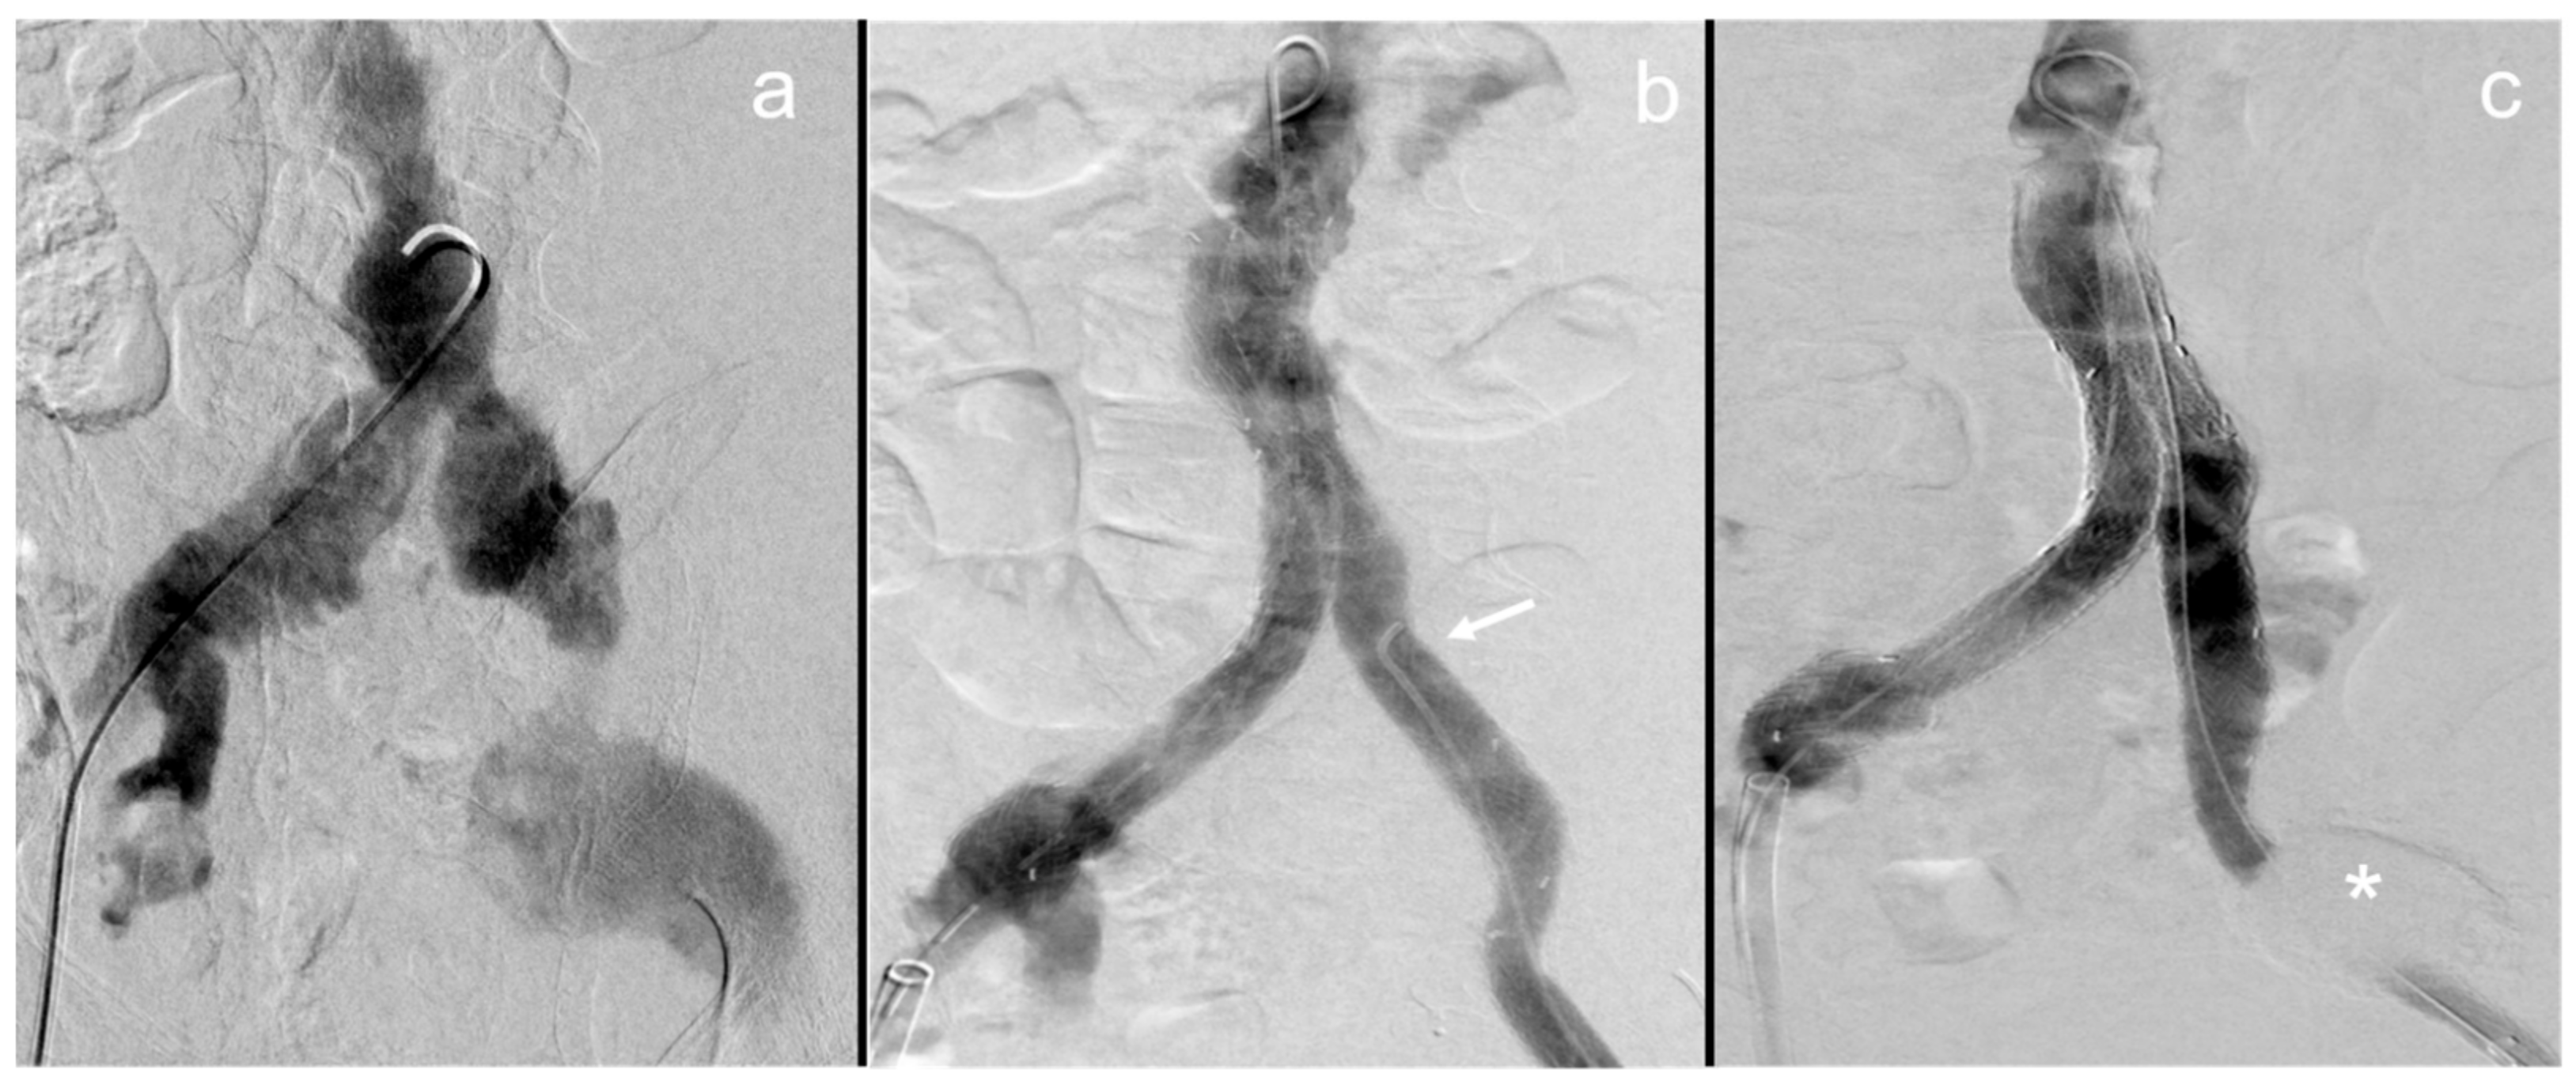

Figure 2.

Dissolution of the NBCA cast in a patient after fenestrated endovascular aneurysm repair of the visceral aorta.

In this patient, fenestrated endovascular aneurysm repair with add-on sac embolization and intentional right renal artery embolization with NBCA were conducted due to visceral aortic aneurysmal rupture. In the immediate postinterventional CT scan, the NBCA–lipiodol cast is seen inside the aneurysm sac and the right renal artery (a). In the follow-up imaging conducted after 26 months, the cast is almost completely dissolved, with only few remaining fragments in the right renal artery (b).